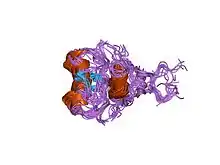

The human GATA1 gene is located on the short (i.e. "p") arm of the X chromosome at position 11.23. It is 7.74 kilobases in length, consists of 6 exons, and codes for a full-length protein, GATA1, of 414 amino acids as well as a shorter one, GATA1-S. GATA1-S lacks the first 83 amino acids of GATA1 and therefore consists of only 331 amino acids.[13][14][15] GATA1 codes for two zinc finger structural motifs, C-ZnF and N-ZnF, that are present in both GATA1 and GATA1-S proteins. These motifs are critical for both transcription factors' gene-regulating actions. N-ZnF is a frequent site of disease-causing mutations. Lacking the first 83 amino acids and therefore one of the two activation domains of GATA1, GATA1-S has significantly less gene-regulating activity than GATA1.[8][15]

In both GATA1 and GATA1-S, C-ZnF (i.e. C-terminus zinc finger) binds to DNA-specific nucleic acid sequences sites viz., (T/A(GATA)A/G), on the expression-regulating sites of its target genes and in doing so either stimulates or suppresses the expression of these target genes. Their N-ZnF (i.e. N-terminus zinc fingers) interacts with an essential transcription factor-regulating nuclear protein, FOG1. FOG1 powerfully promotes or suppresses the actions that the two transcription factors have on most of their target genes. Similar to the knockout of Gata1, knockout of the mouse gene for FOG1, Zfpm1, causes total failure of red blood cell development and embryonic lethality by day 11.5. Based primarily on mouse studies, it is proposed that the GATA1-FOG1 complex promotes human erythropoiesis by recruiting and binding with at least two gene expression-regulating complexes, Mi-2/NuRD complex (a chromatin remodeler) and CTBP1 (a histone deacetylase) and three gene expression-regulating proteins, SET8 (a GATA1-inhibiting histone methyltransferase), BRG1 (a transcription activator), and Mediator (a transcription co-activator). Other interactions include those with: BRD3 (remodels DNA nucleosomes),[18][19][20] BRD4 (binds acetylated lysine residues in DNA-associated histone to regulate gene accessibility),[18] FLI1 (a transcription factor that blocks erythroid differentiation),[21][22] HDAC1 (a histone deacetylase),[23] LMO2 (regulator of erythrocyte development),[24] ZBTB16 (transcription factor regulating cell cycle progression),[25] TAL1 (a transcription factor),[26] FOG2 (a transcription factor regulator),[27] and GATA2 (Displacement of GATA2 by GATA1, i.e. the "GATA switch", at certain gene-regulating sites is critical for red blood development in mice and, presumably, humans).[17][28][29] GATA1-FOG1 and GATA2-FOG1 interactions are critical for platelet formation in mice and may similarly be critical for this in humans.[17]